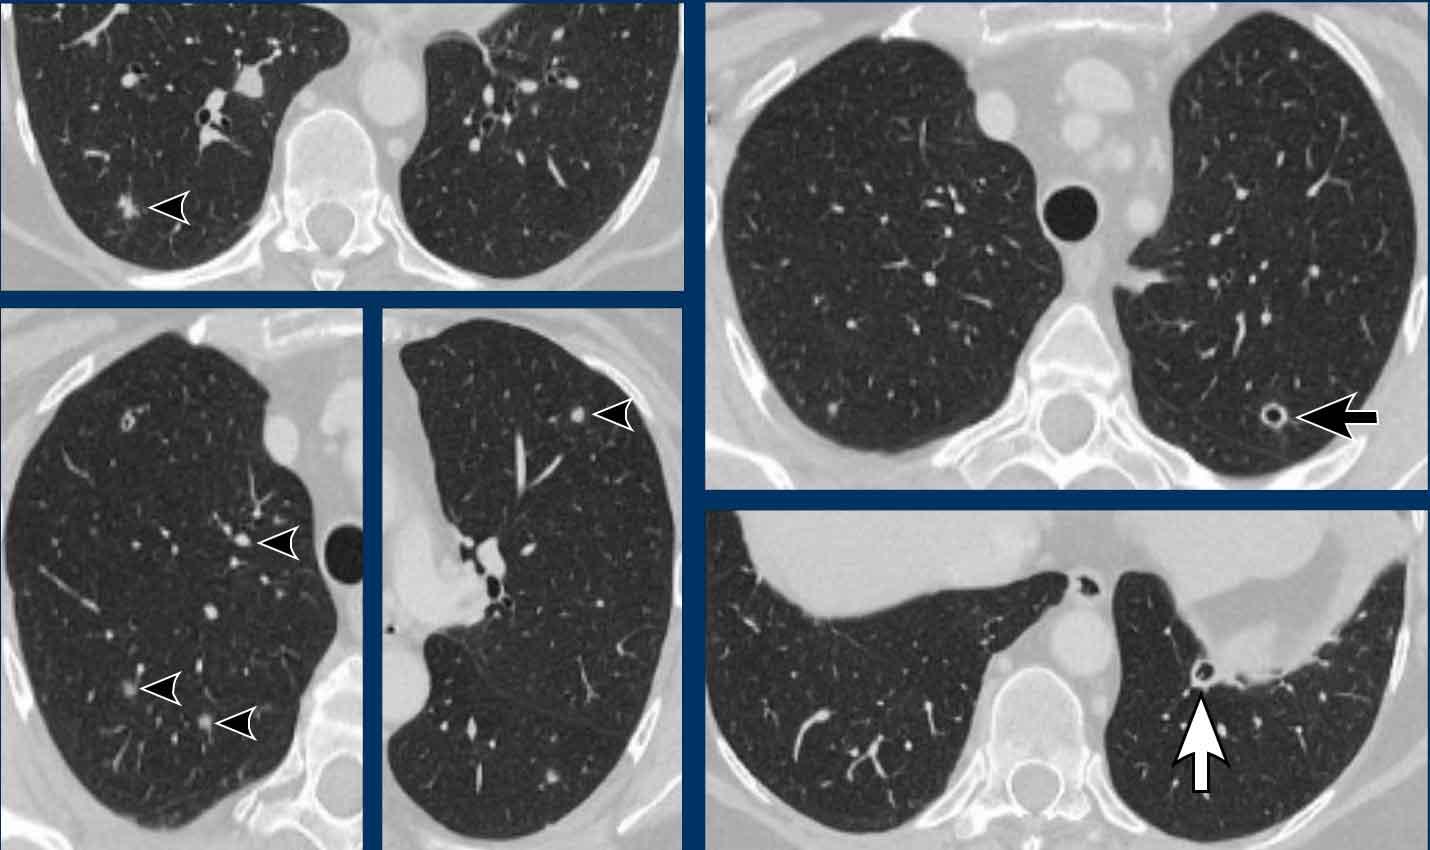

Tổn thương đa ổ

Khi có nhiều hình ảnh trông giống nang, cần phân biệt bệnh phổi dạng nang thực sự với các bệnh lý bắt chước khác (hình minh họa).

- Nhiều nang phổi với thành mỏng ở bệnh nhân LCH giai đoạn tiến triển. Đây là bệnh phổi dạng nang thực sự.

- Khí phế thũng trung tiểu thùy, biểu hiện là các lỗ đen không có thành. Lưu ý dấu hiệu chấm trung tâm (mũi tên). Khí phế thũng có thể là yếu tố gây nhầm lẫn thực sự và sẽ được thảo luận chi tiết hơn ở phần sau.

- Tổ ong (Honeycombing) biểu hiện là chồng các nang thành dày ở ngoại vi thùy dưới ở bệnh nhân xơ phổi.

- Giãn phế quản dạng nang, biểu hiện là các ống dạng nang. Thường không khó phân biệt khi cuộn qua các lát cắt, nhưng đôi khi có thể gây thách thức.